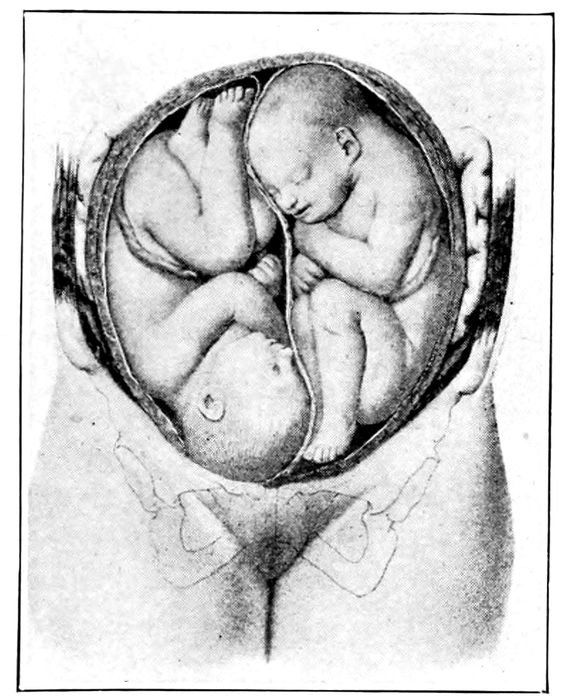

83 |